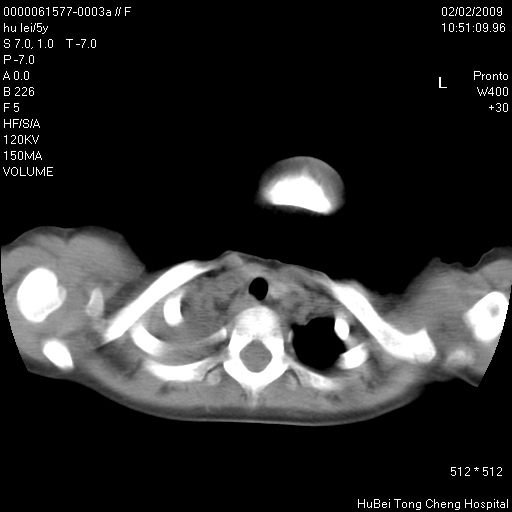

标题: PED1732:M5Y,右肺囊性占位!

患者:男,5。无明显不适,拍胸片考虑右肺囊肿。

行ct扫描,图象如下: